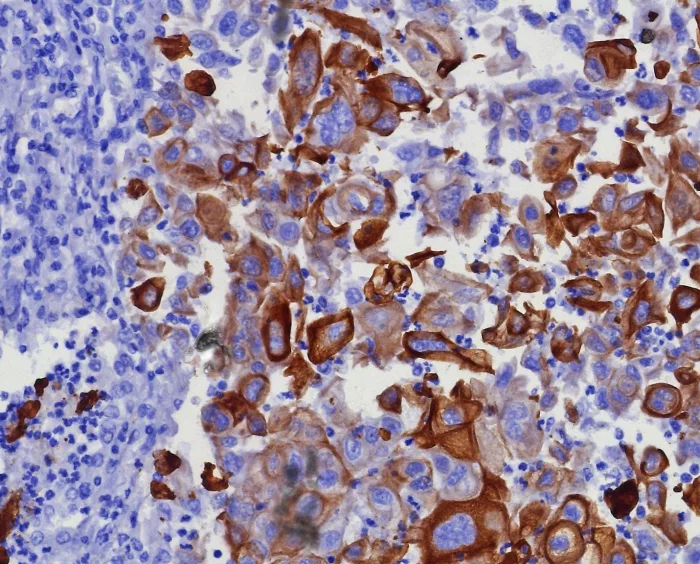

Formalin-fixed, paraffin-embedded human lung adenocarcinoma stained with CK17 Recombinant Rabbit Monoclonal Antibody (KRT17/8346R). HIER: Tris/EDTA, pH9.0, 45min. 2: HRP-polymer, 30min. DAB, 5min.

CK17 is normally expressed in the basal cells of complex epithelia but not in stratified or simple epithelia. Antibody to CK17 is an excellent tool to distinguish myoepithelial cells from luminal epithelium of various glands �such as mammary, sweat and salivary. CK17 is expressed in epithelial cells of various origins, such as bronchial epithelial cells and skin appendages. It may be considered as epithelial stem cell marker because CK17 Ab marks basal cell differentiation. CK17 is expressed in SCLC much higher than in LADC. Eighty-five percent of the triple negative breast carcinomas immunoreact with basal cytokeratins including anti-CK17. Also important is that cases of triple negative breast carcinoma with expression of CK17 show an aggressive clinical course. Additionally, anti-CK17 and anti-MUC1 immunoreactivity represents pancreatobiliary subtype whereas anti-MUC2 and anti-CDX-2 positivity defines intestinal subtype.